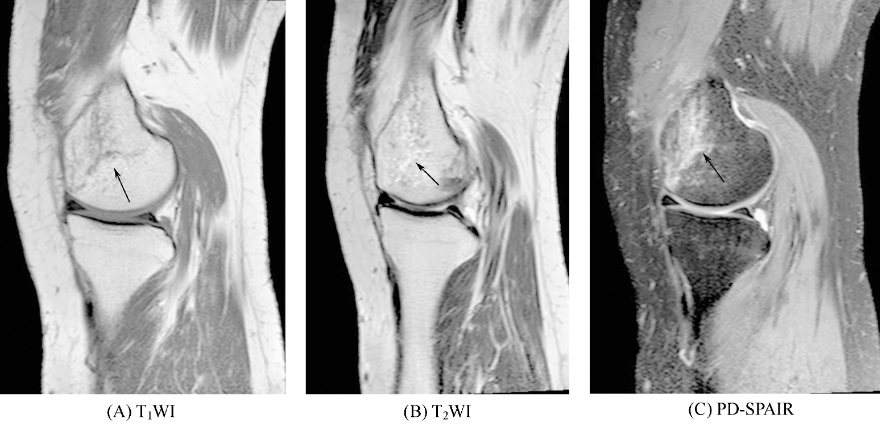

②骨挫伤又称隐匿性骨折,是外力作用引起的骨小梁断裂和骨髓水肿、出血,无骨皮质中断。在平片和CT上常无异常发现。骨挫伤区在T1WI上表现为模糊不清的低信号区,在T2WI上表现为不规则高信号或线状低信号周围高信号,抑脂序列呈明显高信号(图2)。若伴有出血,信号不均匀,且呈现血肿的MRI图像变化规律。病变一般局限于干骺端,也可延伸至骨干。常伴有附近韧带的撕裂。

图2 骨挫伤右股骨内侧髁见模糊片状长T1长T2信号影,PD-SPAIR病变呈明显高信号。